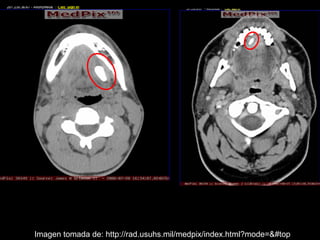

La sialolitiasis es la formación de obstrucciones mineralizadas en las glándulas salivales, causadas por el depósito de calcio y fósforo. Puede presentarse en las glándulas salivales mayores y menores, causando inflamación e hinchazón e incluso dolor durante las comidas. Los sialolitos se ven en radiografías como densidades radiopacas de varias formas y tamaños dentro de los conductos glandulares. El diagnóstico diferencial incluye otras imágenes radiopacas en los tejidos blandos.